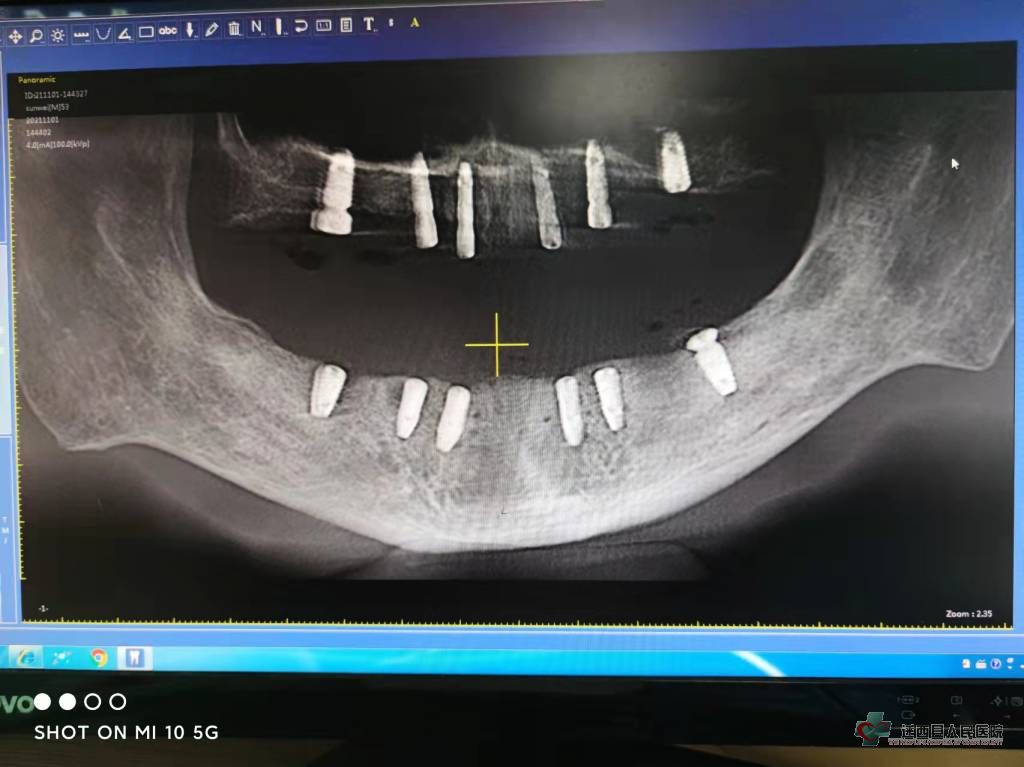

近年来,很多人被牙列缺失所困扰。牙列缺失,不但影响人们的咀嚼和语言功能,还对于面部美观造成了很大程度的影响,有些人甚至因缺失牙齿而不愿张口说话。 为满足患者需求,迁西县人民医院口腔科在医院领导及上级医院的大力支持下,通过外派业务骨干外出进修学习,加强与上级医院专家协作等方式,口腔相关疾病诊疗水平不断提高,特别是种植牙技术已逐渐成熟,截止目前已独立开展种植牙手术近百例,种植牙齿300余颗。在此基础上,于近日与上级医院专家协作顺利完成了1例全口种植牙手术,实现了我县全口种植牙技术的零突破。 患者孙先生,53岁,因牙周病全口牙齿无法保留,拔除后3个月来我院口腔科门诊咨询,经过口腔检查、CBCT检查测量、与患者沟通达成共识,种植导板设计加工、术前病例讨论后,为确保患者生命安全、手术成功 ,做好各种突发情况预案,并请麻醉科刘高飞医师协助应对可能出现的各种紧急情况。在心电监护下,按术前计划流程,术中顺利植入12颗种植体,同期行双侧上颌窦内提升术、多位点植骨术、CGF引导骨再生术等,历时约4小时,术后患者生命体征平稳,为二期修复手术打下良好基础。

植入后CBCT